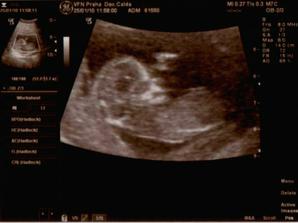

25.1. I.Screaning a první velký UZ,vše je naprosto dokonalé,jsme zdraví.

Dlouho jsem nedopisovala co u nás nového.Tak genetika dopadla na jedničku,máme za sebou echo srdíčka a kontrolu orgánů,a jsem zdraví Lukášek.